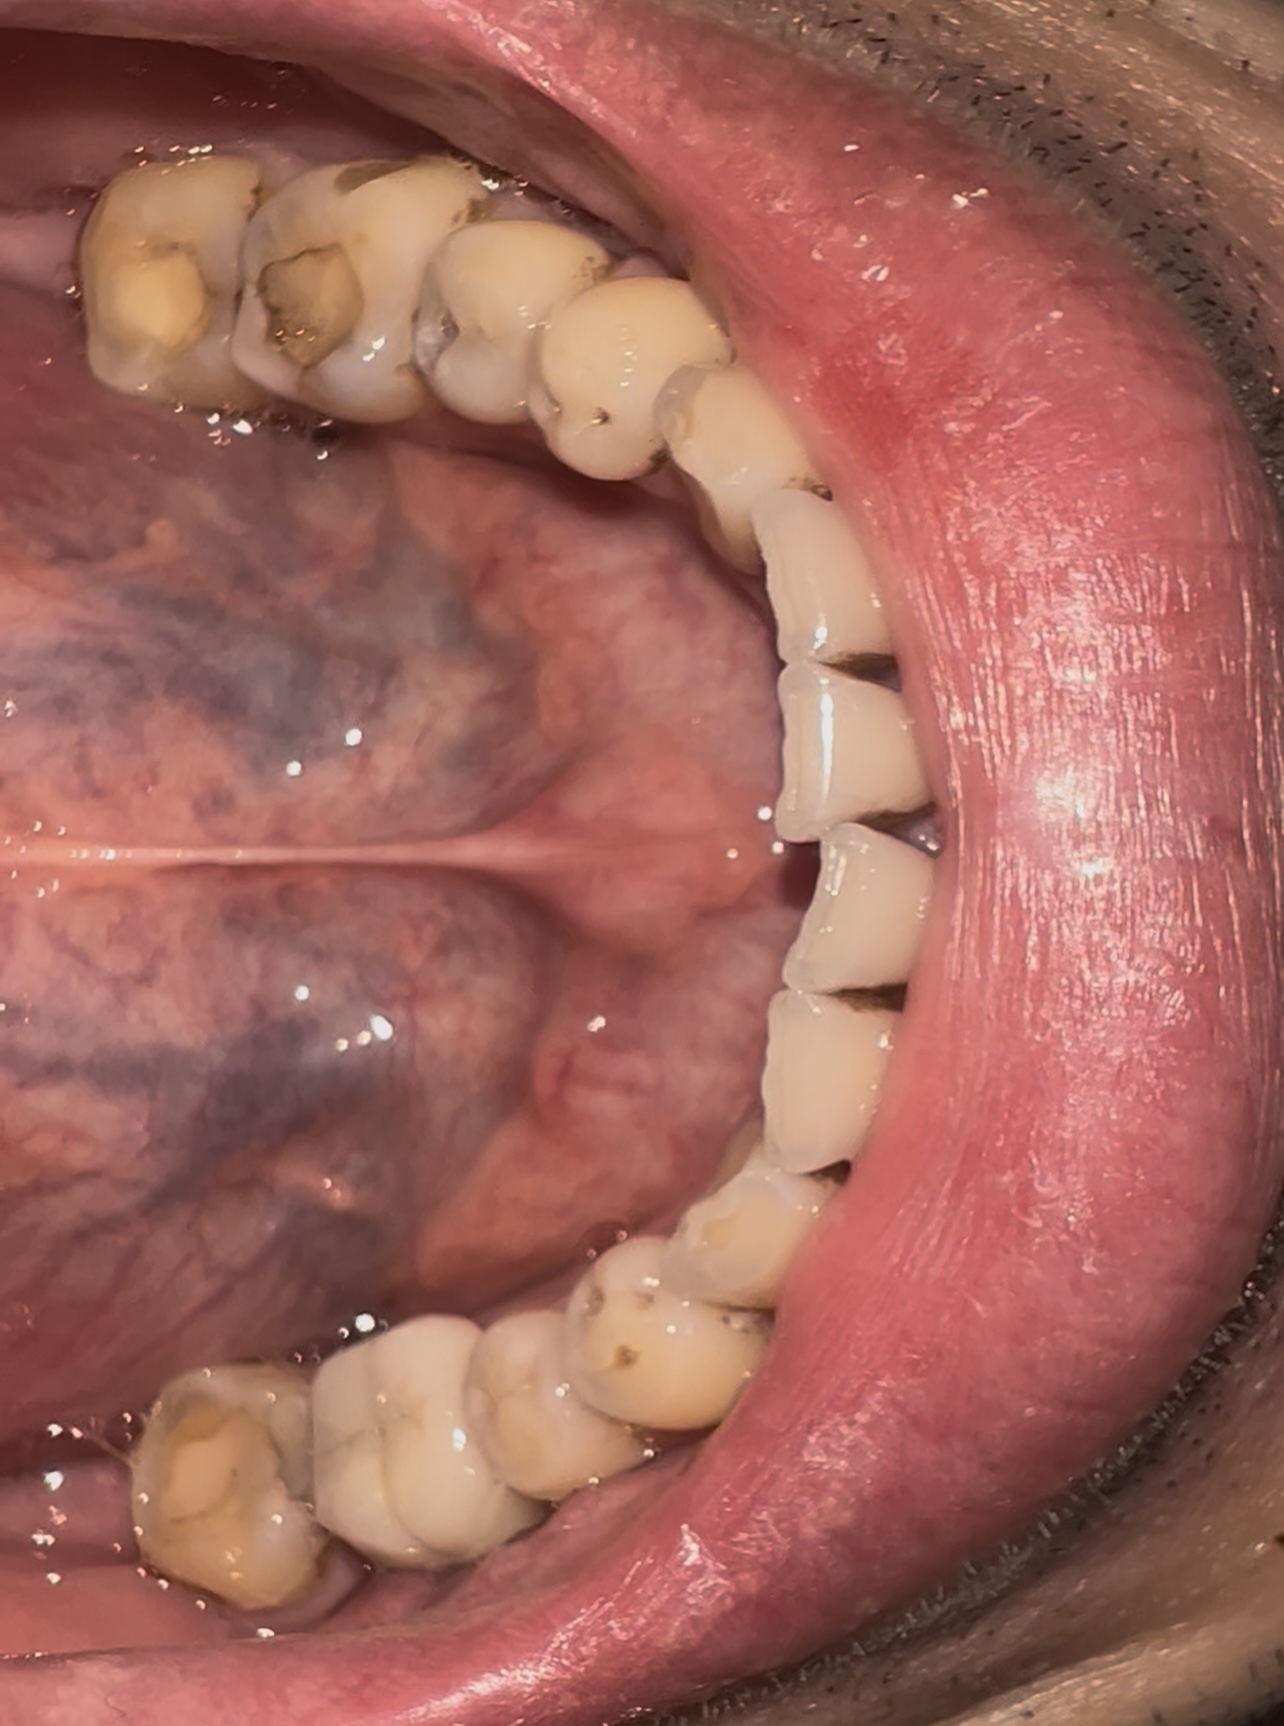

>>1631979 (OP)

сап двач

удалил зубы мудрости в 16 году, а в 17-18 носил брэкеты

жевательные зубы встали в шахматном порядке типо как надо, а вот середина верхней и нижней челюсти не совпадают, ортодонт сказал что все типо ок, сейчас меня начали терзать смутные сомнения - скажите это действительно ок или мне надо бежать к другому и заново выравнивать челюсти по нормальному?

Аноним 19/09/25 Птн 22:34:38 1640572 145